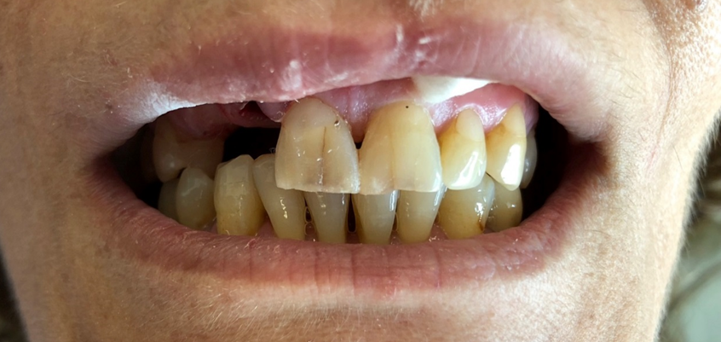

Resident Case Photos

The following are before and after photos of dental patients who have been treated by the residents at NYC Health + Hospitals/South Brooklyn Health. To apply to the program visit the Dental GPR Page and click on Application Information.

Veneers